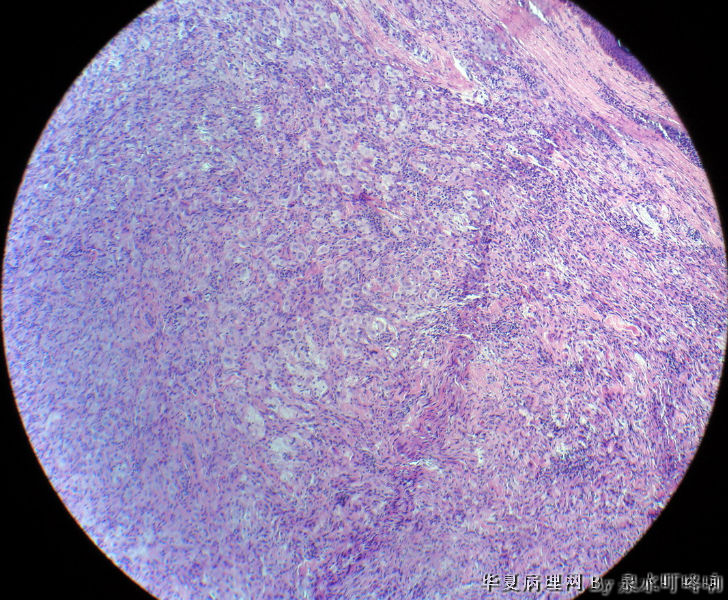

• 颈后部肿物图4

图4

Rosai-Dorfman病

肿瘤较小,梭形细胞间质内可见一些较大细胞,核小,胞质丰富,可见胞质内较多颗粒,考虑颗粒细胞瘤,做免疫组化标记S-100证实。

倾向纤维组织细胞瘤,免疫组化排除颗粒细胞瘤。

病理改变中浸润的细胞考虑组织细胞来源。诊断考虑单发性网织细胞肉芽肿(网织组织细胞瘤)可能。如考虑Rosai-Dorfman病,病理改变中没有明显淋巴细胞浸润和吞噬现象,需要免疫组化来明确诊断。

北京肿瘤医院会诊:纤维组织细胞瘤。